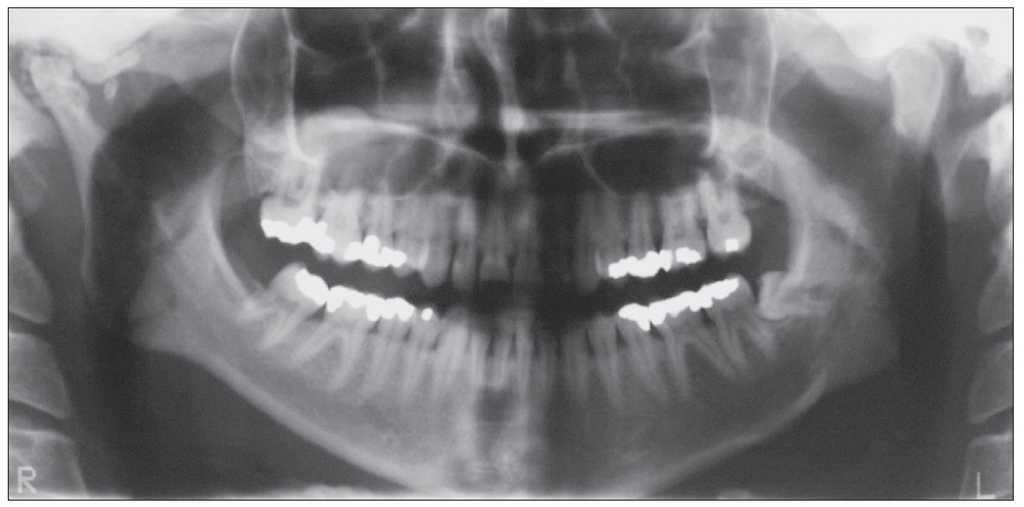

En la radiografía panorámica practicada a una paciente se detectó por casualidad una calcificación en proyección sobre la articulación temporomandibular derecha (fig. 1). La paciente no refirió dolor ni otras molestias.

Figura 1. Radiografía panorámica.